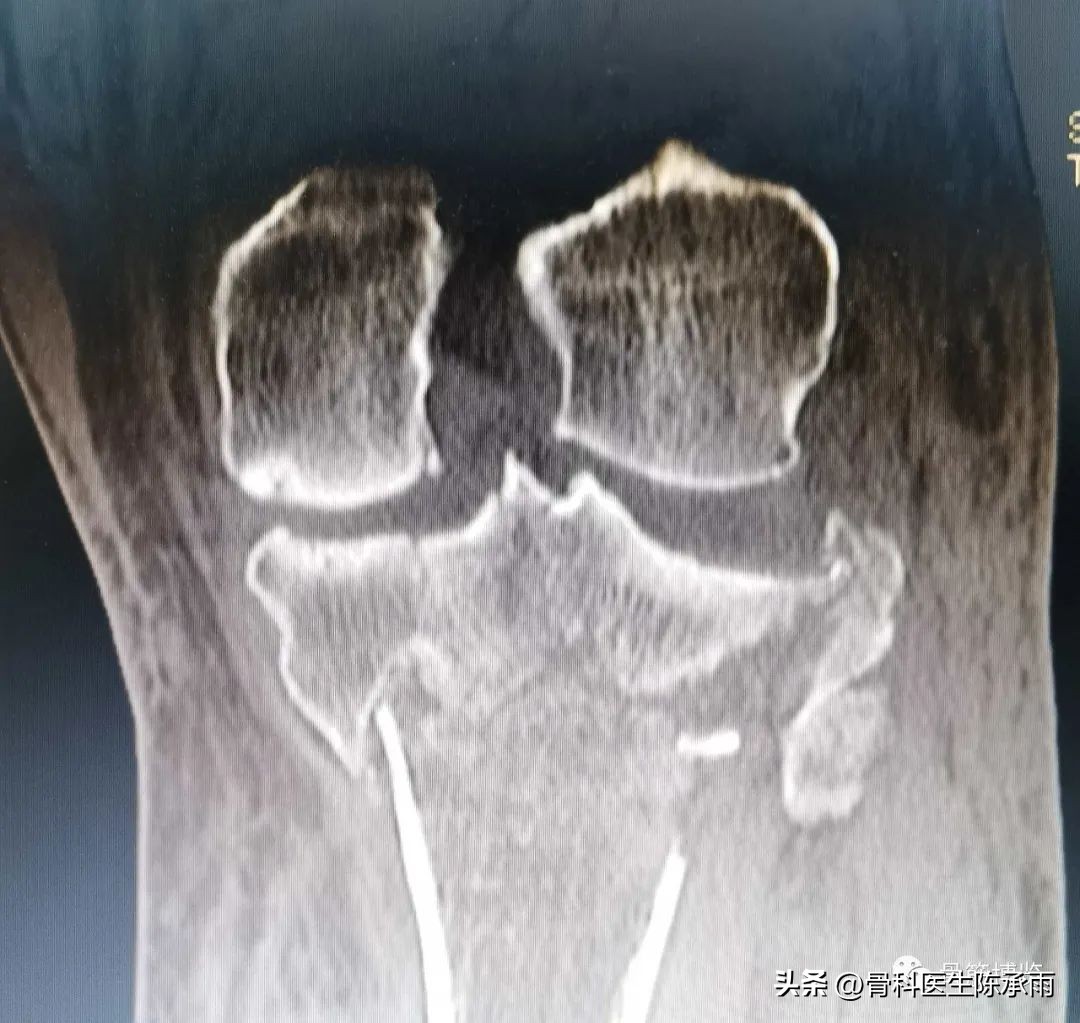

近段时间的胫骨平台骨折,没来得及详细整理

胫骨平台骨折的分型比较多,我们临床上常用的就是Schatzker分型和AO骨折的分型,还有骨折脱位的Hohi-Moore分型,这是我们常用的三个分型。

五型 双髁的骨折,

六型 双髁伴干骺端的骨折,